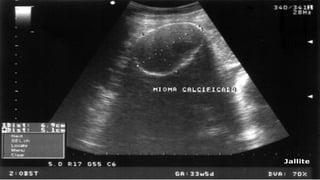

Imagen:

- Ultrasonido vaginal (95-

100% de sensibilidad).

- Estructuras hipoecoicas

o hiperecoicas,

dependiendo del tejido

conjuntivo.

Ruiz, M. E. (2009). Miomatosis uterina. An Med (Mex) , 54, 232-233.

• 24.

Imagen: - Ultrasonido vaginal(95- 100% de sensibilidad). - Estructuras hipoecoicas o hiperecoicas, dependiendo del tejido conjuntivo. Ruiz, M. E. (2009). Miomatosis uterina. An Med (Mex) , 54, 232-233.